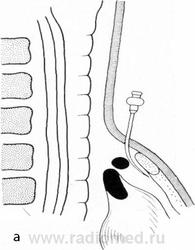

При подозрении на абдоминомедиастинальную липому наиболее достоверные результаты дает пневмомедиастинография. Введение субксифоидальным способом небольшого количества кислорода или воздуха (200 — 300 мл) в нижний отдел переднего средостения обычно позволяет окаймить опухоль светлой полоской и отделить ее от тени сердца и легкого. От диафрагмы опухоль не отделяется, напротив, ее ножка уходит книзу, через отверстие в диафрагме и направляется к передней брюшной стенке, т. е. к скоплению предбрюшинного жира, из которого она берет начало.

Типичным, практически патогномоничным симптомом абдоминомедиастинальной липомы является описанный И. Д. Кузнецовым (1962) и J. Voisin и соавт. (1957) феномен расслоения долек этой опухоли введенным в средостение газом, что приводит к фрагментации ее тени, приобретающей пестрый, неоднородный вид. Другие патологические образования средостения подобной картины не дают.

Тень ножки абдоминомедиастинальной липомы, проникающей через диафрагму в подбрюшинное пространство, также фрагментируется и приобретает ту же структуру, что и тень самой опухоли. Это особенно хорошо видно на боковом снимке, произведенном в положении Тренделенбурга.